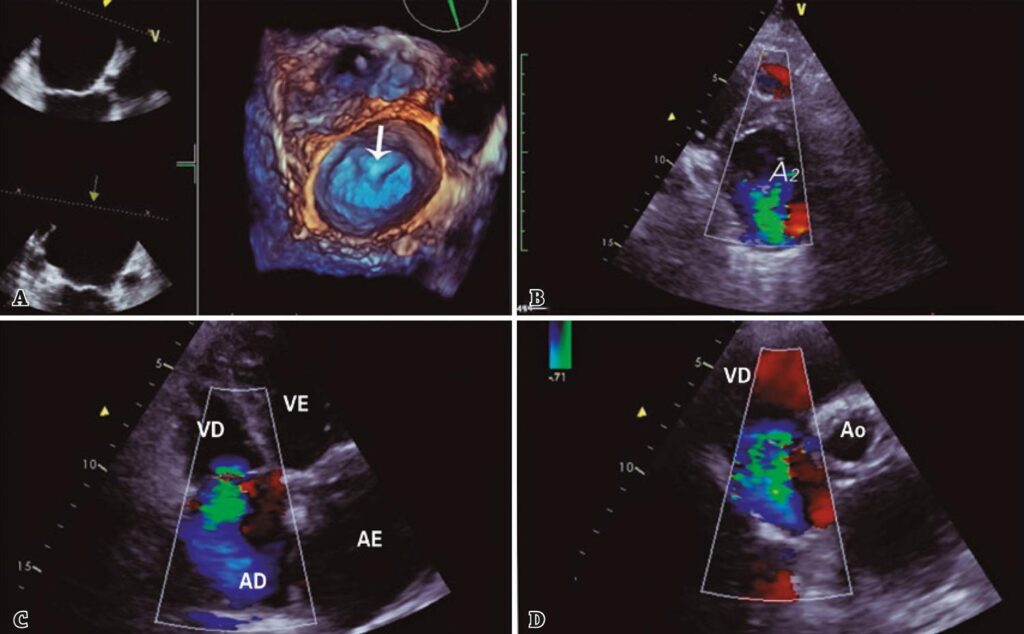

Figura 1

Ecocardiograma transtorácico tridimensional pré-procedimento. (A) Reconstrução tridimensional da válvula mitral mostrando prolapso do folheto anterior no segmento A2 (seta). (B) Visão frontal da válvula mitral mostrando o jato regurgitante central (A2/P2). (C) Corte 4 câmaras mostrando regurgitação tricúspide severa. (D) Eixo curto confirmando regurgitação tricúspide severa.